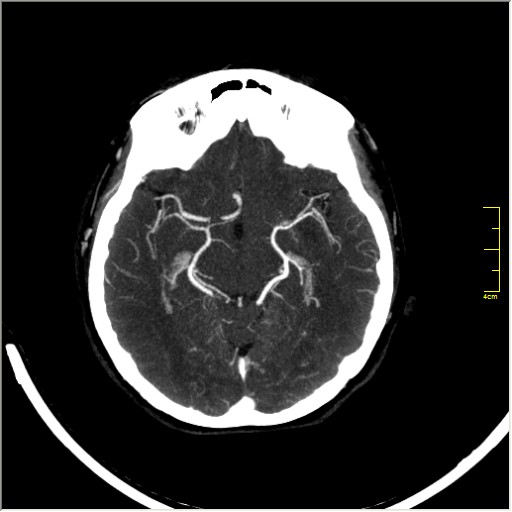

КТ ангиография головного мозга

Стандартная процедура в современной работе КТ кабинета, весьма несложна в исполнении.

Сканы представленны в режиме MIP.

Angio0.JPG

Angio1.JPG

Angio2.JPG

Angio3.JPG

Angio4.JPG